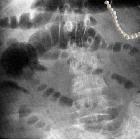

string-of-beads sign

The

"string-of-beads" feature in medial fibromuscular dysplasia. The sign is caused by areas of relative stenoses alternating with small aneurysms. The diameters of the aneurysms exceed the normal diameter of the artery. The sign is characteristic of medial FMD. A similar bead appearance may be seen in perimedial FMD, but the diameters of the beads do not exceed the normal diameter of the artery [10]. Note the involvement of branch renal arteries.